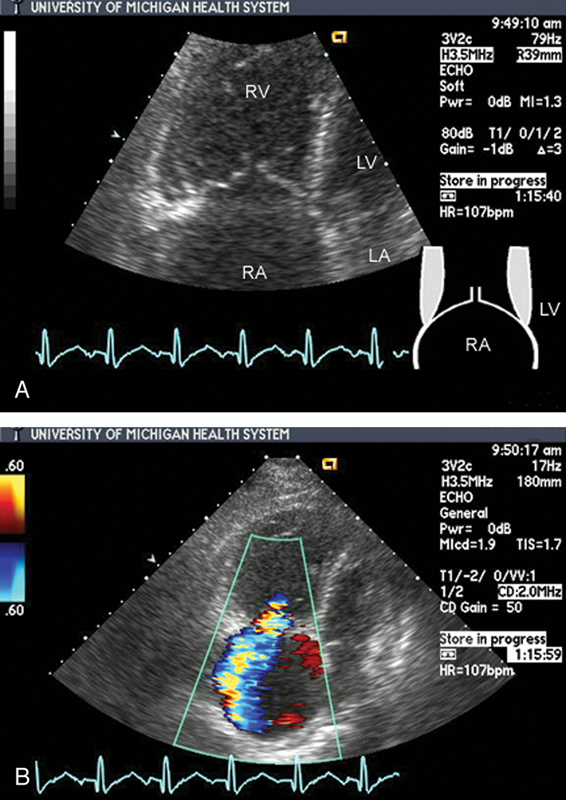

فحوصات تشخيصية لبعض امراض القلب والشرايين التاجية